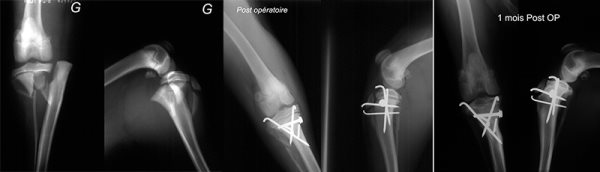

Ostéosynthèse d'une non-union de l'olécrane ancienne de plus de trois mois par utilisation d'une plaque LCP mixte pour vis verrouillées de diamètre 2,4mm en Tête de plaque et 3,5 mm en Queue plaque

- Ostéosynthèse olécrane

- Ostéosynthèse ol"crane chie